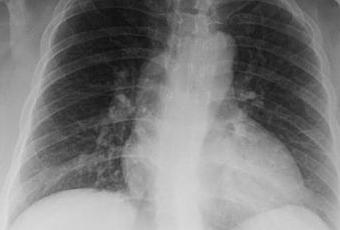

LA PROYECCION RADIOLOGICA OBTENIDA NOS MUESTRA LOS SIGUIENTES HALLAZGOS:

-Tejidos blandos, con densidad conservada, simétricos, sin evidencia de alteraciones.

-Estructuras óseas, sin evidencia de lesiones líticas, blásticas o perdida de la contigüidad.

-Vía aérea permeable, con leve desplazamiento de la tráquea hacia derecha.

-Cardio-mediastino, con aparente engrosamiento a nivel hiliar, de predominio derecho. Así como aparente aumento del tamaño cardiaco, el cual no se considera con valor diagnóstico, por el tipo de proyección.

-Hilio pulmonar derecho, con presencia de adenopatía. Hilio pulmonar izquierdo sin alteraciones.

-Trama bronco-vascular, con leve aumento de su densidad hacia regiones basales y para-hiliares, de predominio derecho.

-Campo pulmonar derecho, con pequeña área de consolidación, con presencia de broncograma aéreo a nivel basal. Campo pulmonar izquierdo sin alteraciones.

-Recesos cardiofrénicos y costofrénicos, sin alteraciones.

OPINIÓN RADIOLÓGICA:

-EN EL PRESENTE ESTUDIO RADIOGRÁFICO, CON IMAGEN QUE SUGIERE, APARENTE FOCO NEUMONICO A NIVEL BASAL DERECHO, CON PRESENCIA DE ADENOPATIAS HILIARES DERECHAS.

-CORRELACIONAR CON DATOS E HISTORIA CLINICA DEL PACIENTE